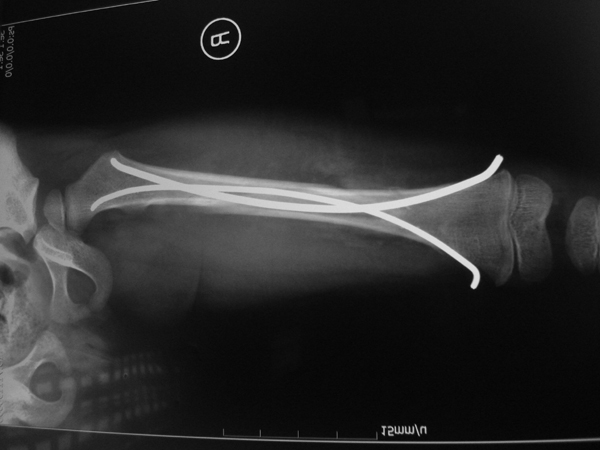

骨折及创伤:采用闭合穿针内固定、应用弹性髓内针治疗股骨、胫骨等长骨骨折,运用可吸收螺丝钉治疗骨端骨折,具有创伤小、骨折愈合快、皮肤外观好、功能恢复快的特点。

图5.儿童股骨干骨折手术前

图6.股骨骨折微创弹性髓内针固定,*********的骨折治疗方法。